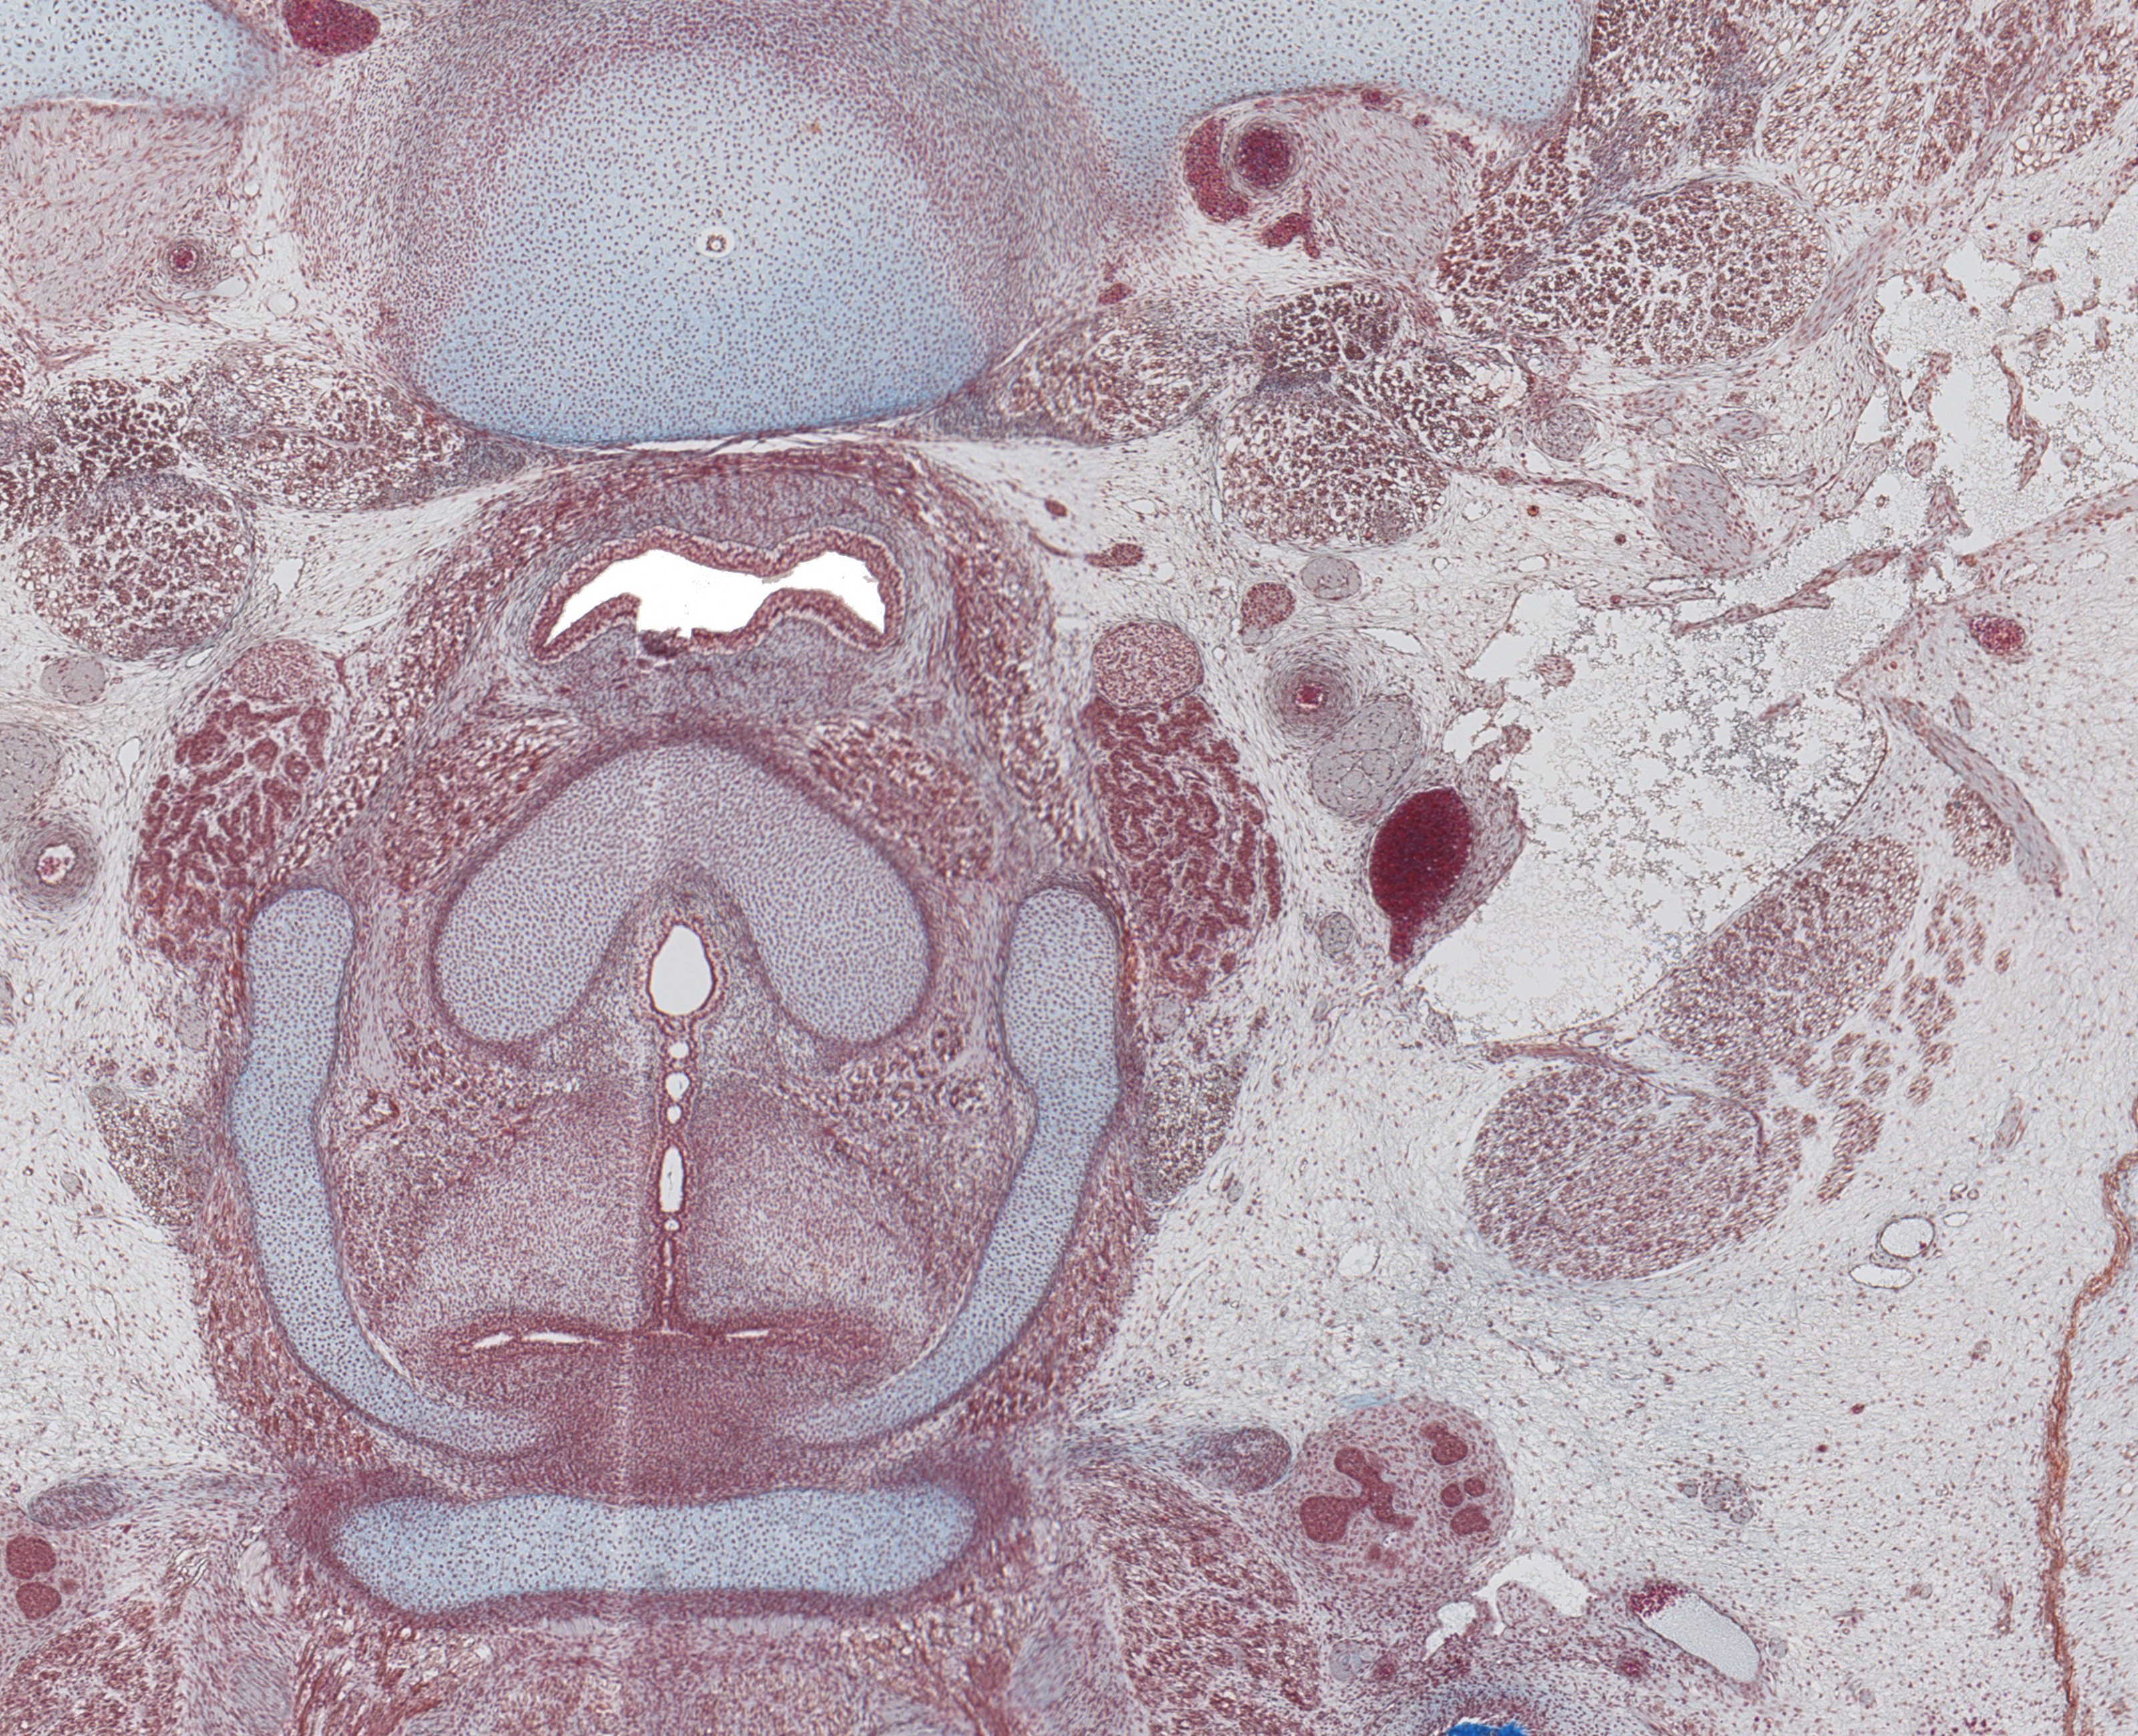

Tissue

Larynx and Sup. Parathyroid Gland

Carnegie Embryo #9226

80-01-01